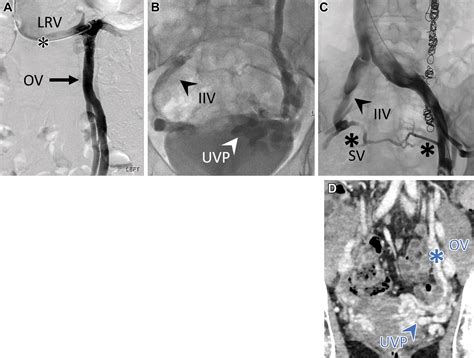

• Imaging tests: Various imaging tests may be used to visualize the veins and assess blood flow. These tests include:

Venography Involves injecting a contrast dye into the veins to visualize them on X-ray images.

Magnetic Resonance Venography (MRV) Uses magnetic resonance imaging to create detailed images of the veins.

These tests help healthcare providers identify the location and extent of venous insufficiency and plan appropriate treatment.

• Embolization: A procedure where a catheter is used to insert a small coil or plug into the affected vein to block blood flow and redirect it to healthier veins.

• Venous stenting: Placement of a stent in the vein to keep it open and improve blood flow.